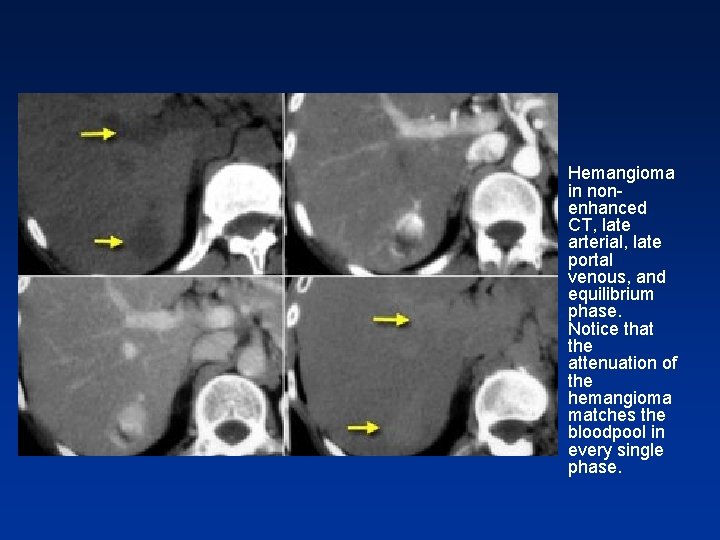

• Hemangioma in nonenhanced CT, late arterial, late portal venous, and equilibrium phase. Notice that the attenuation of the hemangioma matches the bloodpool in every single phase.